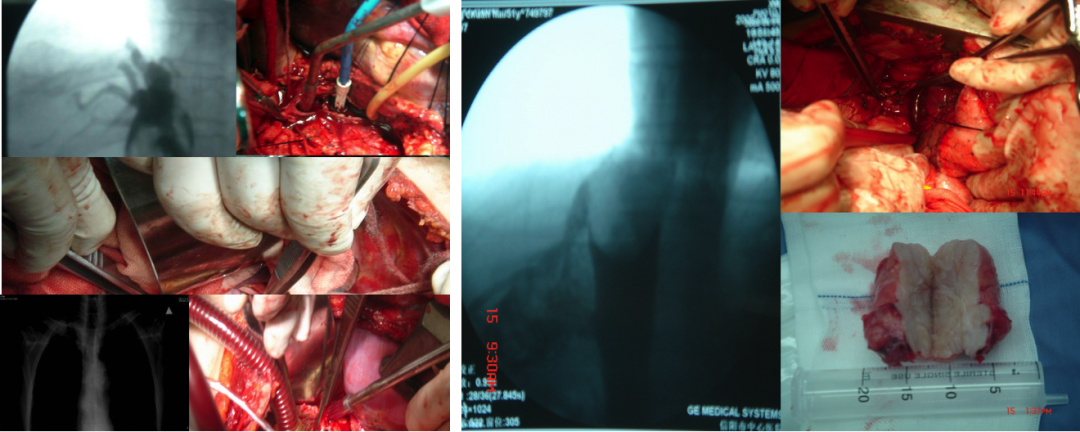

【肝段下腔静脉全程显露的布加综合征根治术】

手术核心步骤

采用双向游离技术:

经第6或第7肋间开胸,打开心包,暴露肝上段下腔静脉。

切开膈肌,向上游离至右心房,向下游离至肾上段下腔静脉。

右心房插管连接体外循环吸引器,术野出血被同步回输入右心房。

全程显露肝段下腔静脉后壁,直视下切除隔膜、血栓或取出异位支架。

【六大优势与创新】

优势一:切彻底

可切除范围包括:

肝下段下腔静脉隔膜

下腔静脉双隔膜

隔膜远端继发血栓

突入右心房的下腔静脉支架

直视下无残留,避免二次手术。

优势三:少出血

体外循环辅助下的右心耳插管法:

术野出血由术者控制的吸引器吸入,同步回输至右心房。

无需新增切口建立体外循环。

实现“出多少血,同步回输多少血”,极大减少失血。

优势四:探病因

术中直接观察和病理分析带来了对BCS病因的全新认识:

观察到血栓向隔膜演变的迹象:附壁血栓逐渐机化、纤维化,最终形成隔膜。

复发病例可见新生隔膜(例如:原为下腔静脉血栓,7年后复发为隔膜)。